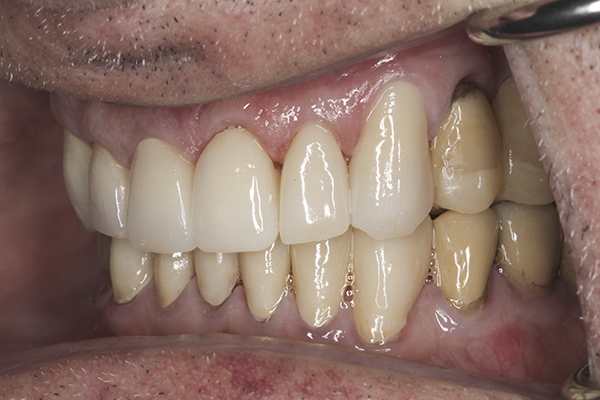

(35.) Postoperative right lateral, closed view.

Figure 35